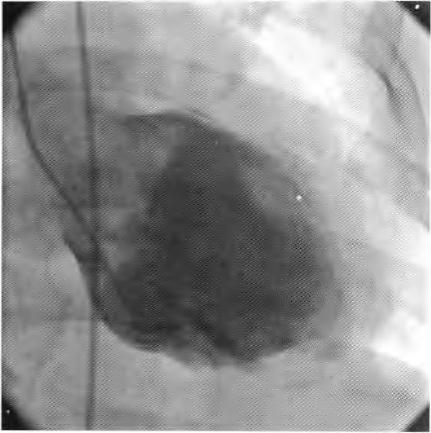

患者择期于10月25日行冠状动脉介入治疗,术前常规给予地塞米松10 mg静脉注射,右侧桡动脉穿刺成功后,经鞘管送多功能造影导管至主动脉窦部,对比剂选择碘帕醇(商品名:碘必乐),导管“吾烟”后数秒钟,患者血压骤然降低至50/30 mmHg,心率逐步增快至90次/min左右,予羟乙基淀粉130/0.4氯化钠注射液(万汶)加压快速静脉滴注100 mL,反复3次静脉注射多巴胺3 mg,血压65/40 mmHg左右,约3 min后心率降至40次/min左右,监护示室性逸搏心律,继之心跳、呼吸骤停。持续胸外按压,气管插管机械通气,持续静脉泵入肾上腺素0.2仙g/(kg•min),并间断4次静脉注射肾上腺素0.5 mg,血压维持在105/50 mmHg左右,进一步行左室造影,见图1。以及左冠状动脉造影,见图2。氧饱和度降至75%,考虑对比剂致高敏反应,引起过敏性休克,静脉滴注甲泼尼龙500mg,经右侧股动脉路径行主动脉内球囊反搏术(intra.aortic balloon pump,IABP)治疗,同时联系外科、麻醉科、体外循环科经左侧股动脉一股静脉行体外膜肺氧合(extra—corporeal membrane oxygenation,EC—MO)支持治疗。ECMO置人后将患者由导管室转送至冠心病监护病房(coronary care unit,CCU)继续抢救治疗,床边心脏超声,见图3。提示室间隔水肿(厚度1.53 cm)。在置人ECMO初期维持绝对镇静,下调直至停用血管活*药性**物,心律以室性逸搏心律为主(持续约48 h),偶然有室速、室颤发作,未作处理。在置人ECMO第3天因急性肾衰竭行床旁连续静脉静脉血液滤过(continuous veno—venous hemofiltration,CVVH)治疗,第4天后患者心率、血压稳定,复查心脏超声提示左心室射血分数40%,撤除ECMO,此后依次拔除气管插管、撤除IABP以及停止CVVH等治疗,患者恢复良好,于11月14日出院。

图1 左室造影未见造影剂外渗至心包腔。心室几无收缩

在冠状动脉介入诊疗术中发生心脏骤停,针对尚处于心肌梗死(尤其是急性ST段抬高型心肌梗死)急性期的病例,要首先考虑心肌梗死后机械并发症(如心室游离壁破裂、室间隔穿孔等)、冠脉急性血栓栓塞事件以及医源性冠脉损伤等,并迅速行相关检查措施排查,如能排除以上危重情况,则要考虑对比剂导致过敏性休克。该患者术中左室造影排除心室游离壁破裂,左冠状动脉造影排除左主干或左冠血管急性血栓栓塞事件以及医源性冠脉损伤,再结合患者存在药物(多种抗生素)过敏史,因此,诊断对比剂致过敏性休克明确。后期心脏超声提示“心肌水肿”,亦是器官组织对过敏的一种表现。